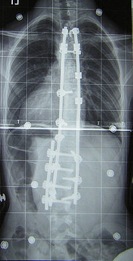

1. Surgery is typically indicated in curves of greater than 45-50 degrees that have a likelihood of progression, curves in patients with spina bifida and cerebral palsy, and curves that affect physiologic function (such as those that inhibit lung expansion and put pressure on the heart). A number of surgical procedures have been developed to correct scoliosis. Modern spinal surgeries use mechanical systems of rods, screws, hooks and wires to correct both lateral and rotational defects.

Thoracic dextroscoliosis (convexity to the right)

and lumbar levoscoliosis (convexity to the left).

This X-ray was taken with the patient laying face down.

Same patient after corrective surgery.